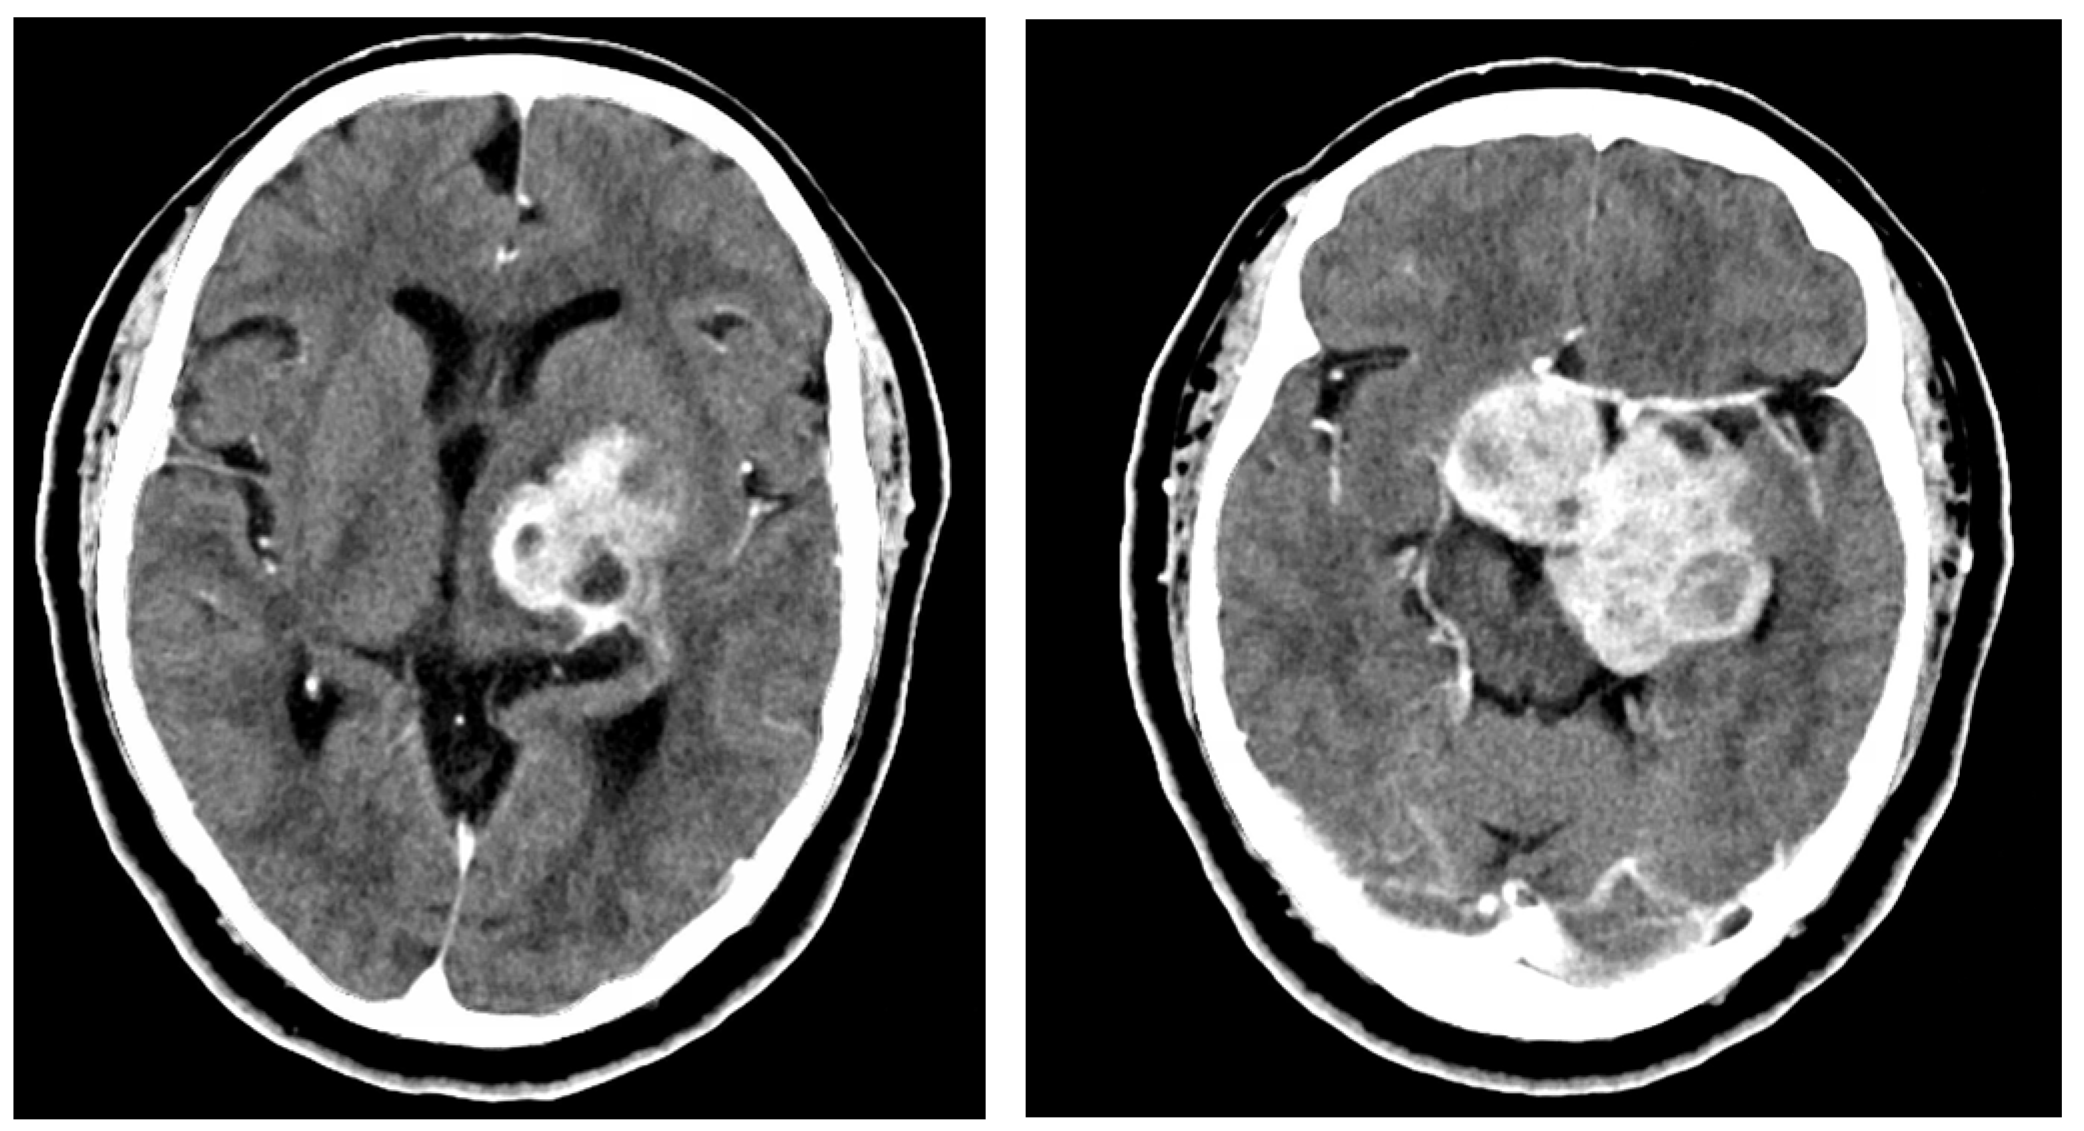

2.1. Case 1

2.2. Case 2